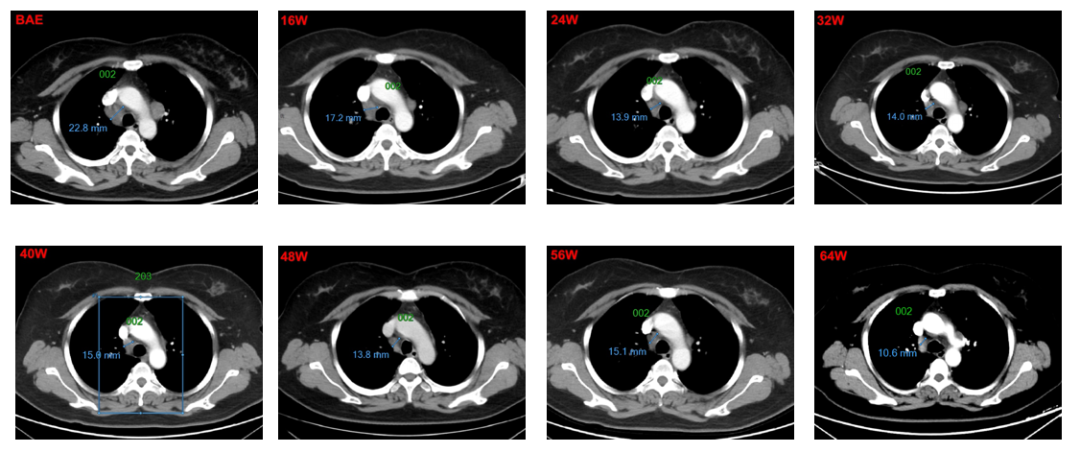

2015-06-18,接受肝左叶切除术,切缘阴性,术后恢复良好。2016.11,复查CT提示双肺结节增大,考虑双肺转移。2016-11-28,患者首次接受多纳非尼治疗(0.2g,每日两次口服),治疗初期,靶病灶显示轻微缩小,经评估为疾病稳定(SD),继续接受多纳非尼治疗,靶病灶持续缓解,经评估疗效达到部分缓解(PR)。整个治疗期间,独立审查委员会(IRC)评估的患者最佳疗效为SD,但研究者评估的最佳疗效为PR。同样,经IRC和研究者评估的无进展生存期(PFS)分别为为11.2个和15.1个月。

1号靶病灶为纵膈淋巴结,8w-40w,靶病灶整体被评为SD,48-64W整体被评为PR;

靶病灶影像学改变: